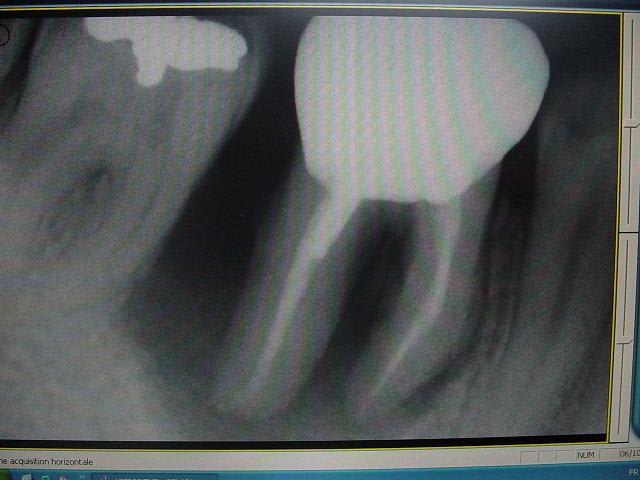

voici un cas paro qui me pose problème: Homme 39 ans, non fumeur, exellente santé ( spotif +++). PAJ dans un mauvais contexte occlusal ( bout à bout et contact essentiellement en posterieur. Je suis un peu paumé sur ce coup là! surtout sur le devenir des molaires. Des pistes avant d'en parler à nice? merci

ci joint des retro de mars 2001 et aout 2003 de 46 qui montre l'evolution du cas..

bon, je suis loin d'etre d'acc avec vous consernant l'endo: regardez l'evolution de la lesion, de 2001 à 2003, sur les retro: il me semble très peu probable que l'endo ( pas top, ok mais d'apparence pas si tocarde) soit en cause. On voit en 2001 une atteinte distale, clairement paro.